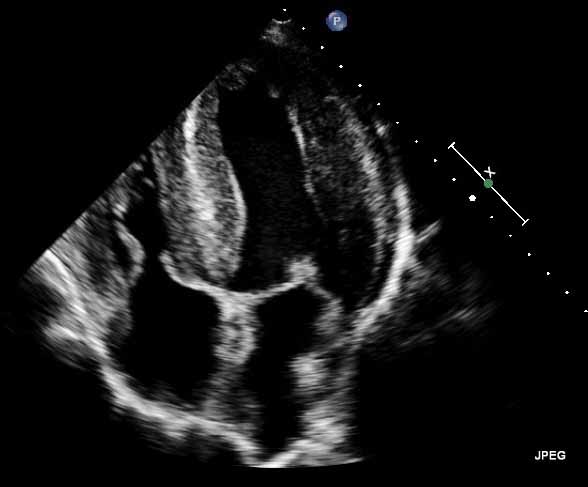

Refer to caption

(a) Heart

Figure 1: Example ultrasound images from the cardiac (a), gastric (b), fetal (c) and Blood flow (d) domain.

Different anatomic regions have different characteristics in ultrasound images, as can be seen in Figure 1. For instance, in a liver scan one might look for tumors using a high-resolution abdominal 2D probe. For heart infarctions, the doctor might need to examine the strain in the heart muscle to detect defect muscle tissue. The wide spread in tissue and pathology difference lead to anatomically specific visualization techniques.